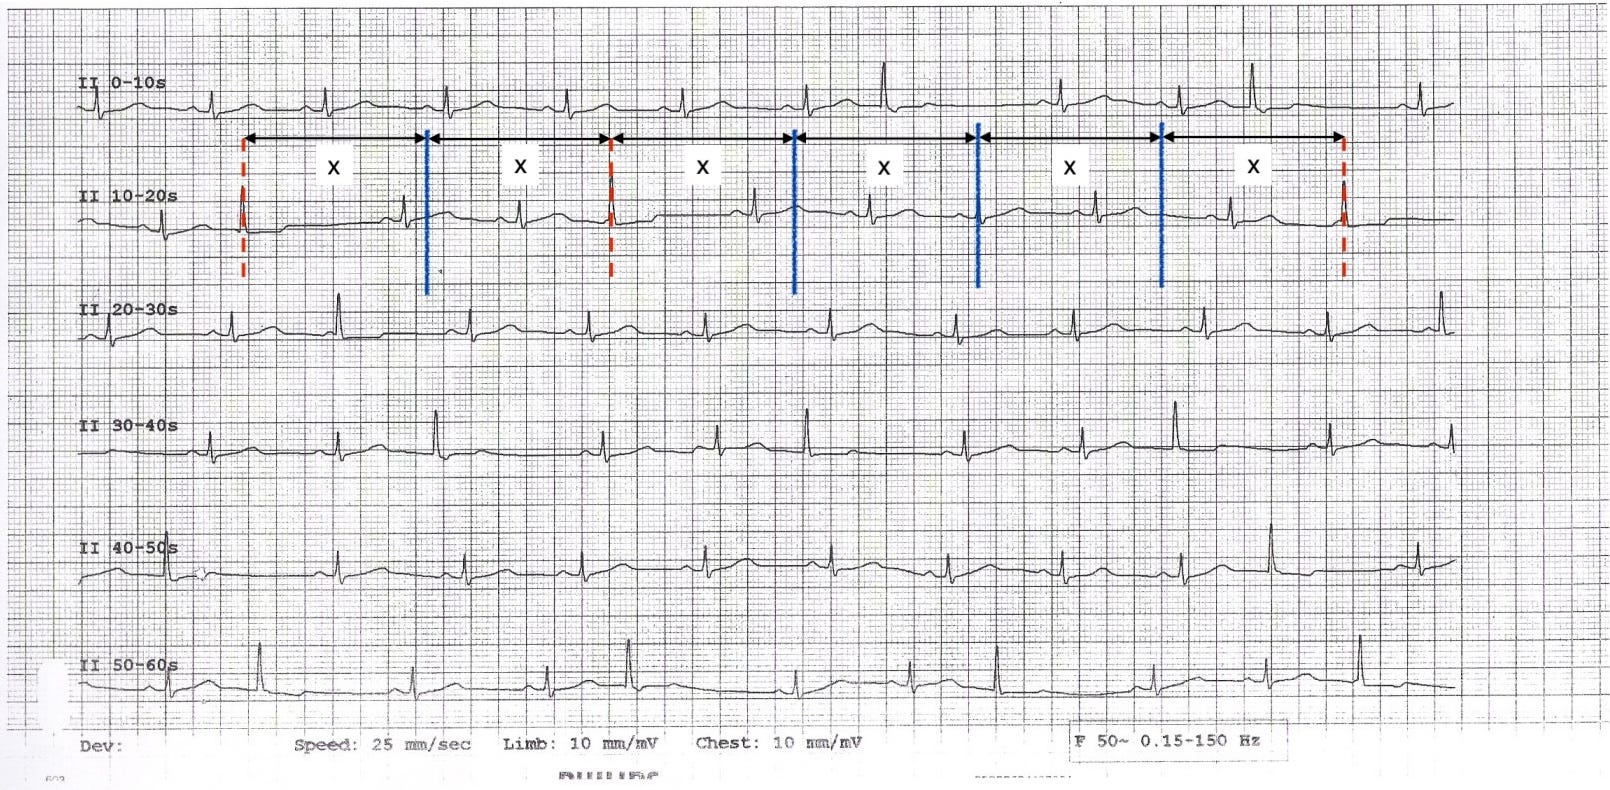

Paper speed: 25 mm/s and voltage: 10 mm/mV (confirmed on printout).

Rhythm: Sinus rhythm with intermittent ectopic beats. The ectopic beats are monomorphic. The coupling intervals between sinus beats and ectopic beats vary.

Overall, sinus rhythm with intermittent monomorphic ectopic beats at variable coupling intervals, consistent with parasystole.

Note: the fifth QRS complex in the bottom rhythm strip is an ectopic beat that appears to be preceded by a P wave. This is most likely a sinus P wave that coincided with the ectopic focus firing. The ectopic beat has the same QRS morphology as the other ectopic complexes, confirming it was driven by the ectopic focus, not by the sinus impulse.

Three diagnostic criteria follow directly from this one mechanism. All three are visible on a 60-second lead II rhythm strip from the same patient:

1. Interectopic intervals are multiples of a common denominator. If the ectopic focus really is an independent clock, it fires at a fixed cycle length (call it X). The intervals between consecutive visible ectopic beats should all be multiples of X (1X, 2X, 3X…). They are.

On the annotated strip below, vertical lines mark each ectopic firing: blue solid lines where the impulse successfully depolarised the ventricles, and red dashed lines where it fired but couldn’t escape (exit block). The gaps between visible beats vary, but every one is a close multiple of the same base interval X (small variations in the ectopic firing rate are normal and expected).

2. Variable coupling intervals. Because the ectopic focus fires on its own schedule, the gap between a sinus beat and the next ectopic beat depends entirely on where in the ectopic cycle the sinus beat happened to fall.

On the annotated strip below, two coupling intervals are marked: "y" (red arrow, first strip) and "z" (blue arrow, fourth strip). They are visibly different lengths. This is the feature that distinguishes parasystole from ordinary premature ectopic beats, where the coupling interval is fixed.